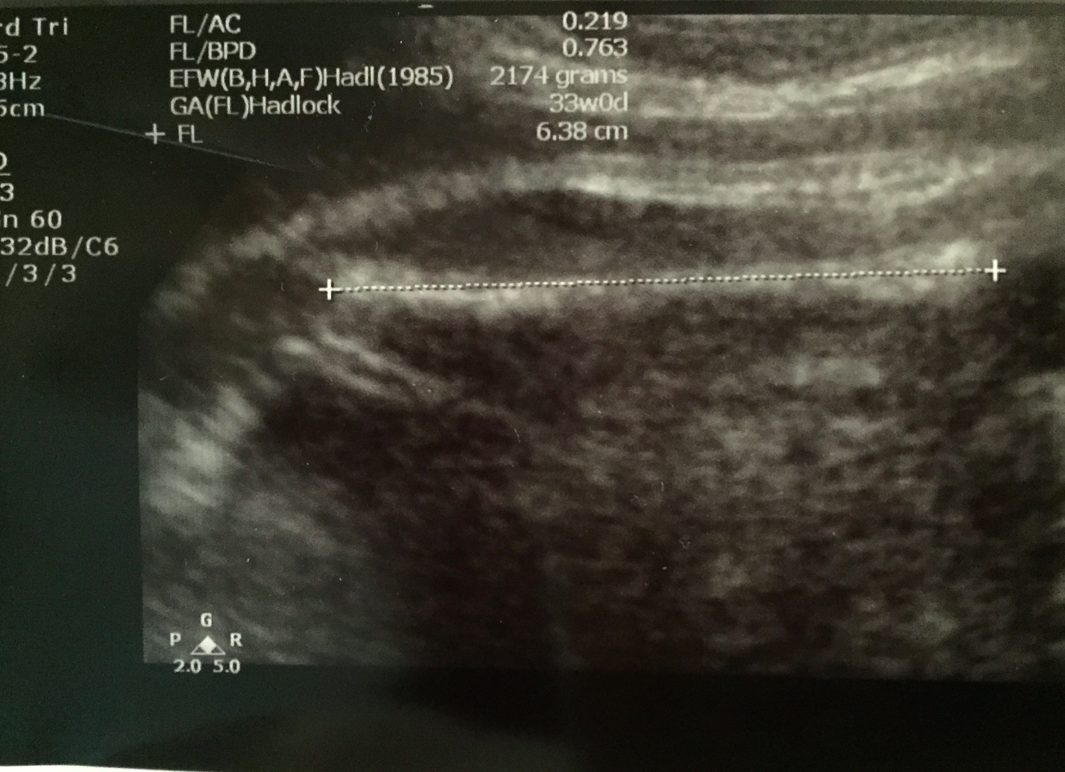

仲有腿長都ok~不過plot落graph度睇就更有意思了,記得睇到尾丫﹗

個graph plot出嚟同之前都好consistent丫﹗頭仔一直都along 50 percentile,肚圍同腿長都比較大少少,relatively好似真係好長腿喎~今日用算式計出嚟嘅估計體重係2.26kg﹗都有啲手感啦~